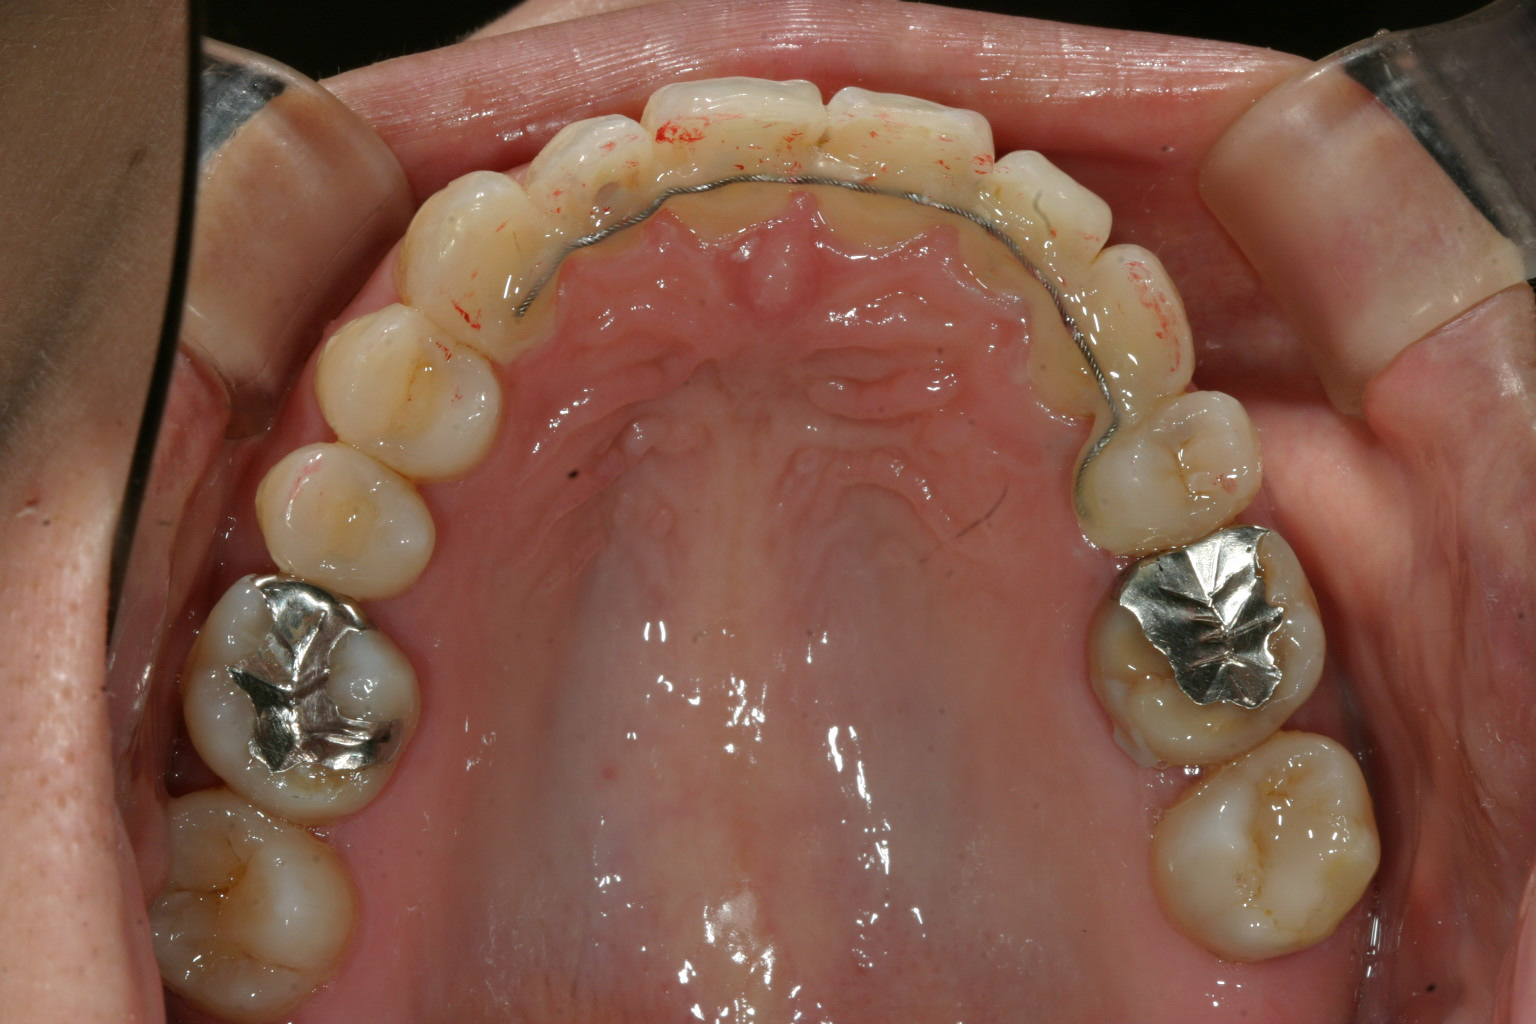

あとは上顎の歯のねじれ改善、下顎の舌側転移も難なく出っ歯も改善しました。

リテーナーとして裏側からワイヤーで留めています。